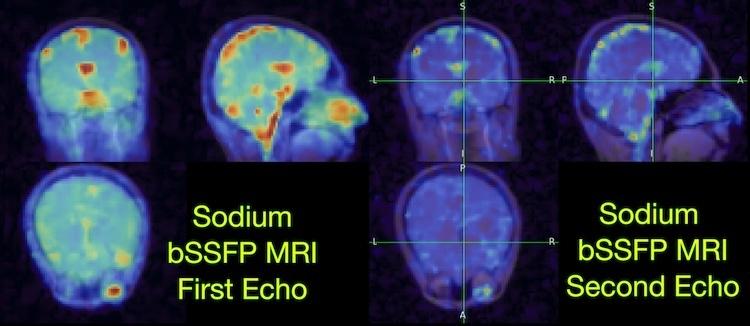

Dec. 1, 2025 — Researchers at the University of California, Berkeley and University of California, San Francisco have ...